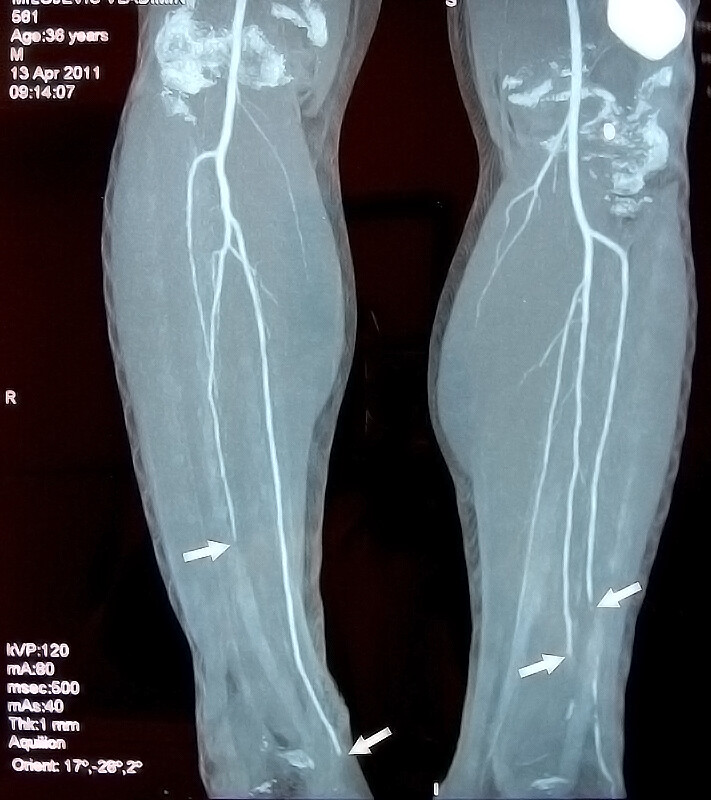

BUERGER’S DISEASE Angiography Diseases And Disorders Smoking And Buerger's Disease It has been suggested that the. Buerger’s disease (thromboangiitis obliterans) is a rare disease most often found in those who smoke. The association of buerger’s disease with tobacco use, particularly cigarette smoking, cannot be overemphasized. The rates of buerger disease are highest in areas of the mediterranean, middle east and asia where heavy smoking is most common. Among people with. Smoking And Buerger's Disease.